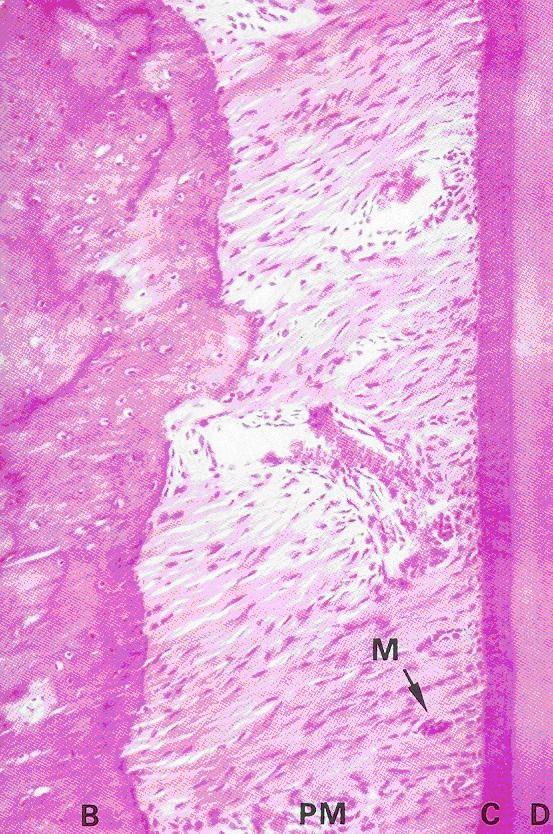

| Fig. 13.8 |

Young and Heath p. 243 |